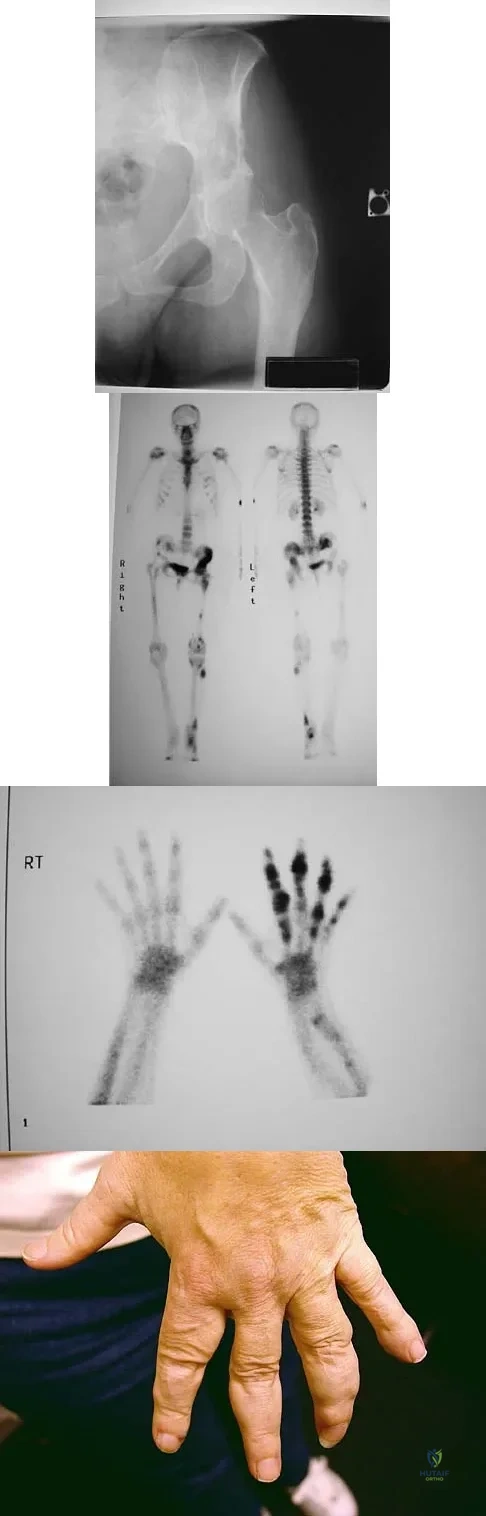

A 74-year-old woman has had acute medial right knee pain for the past 3 months. She denies any history of trauma or previous problems. Coronal and sagittal MRI scans are shown in Figures 11a and 11b. What is the most likely diagnosis?

Explanation

Spontaneous osteonecrosis of the medial femoral condyle is seen in the MRI scans, and is most common in women older than age 60 years. Although usually present in the weight-bearing portion of the medial femoral condyle, spontaneous osteonecrosis has also been described involving the lateral femoral condyle and patella. Most patients are seen postcollapse, and the treatment of choice is arthroplasty. Optimal treatment in precollapse stages is controversial. Kidwai AS, Hemphill SD, Griffiths HJ: Spontaneous osteonecrosis of the knee reclassified as insufficiency fracture. Orthopedics 2005;28:236,333-336. Soucacos PN, Xenakis TH, Beris AE, et al: Idiopathic osteonecrosis of the medial femoral condyle: Classification and treatment. Clin Orthop 1997;341:82-89.